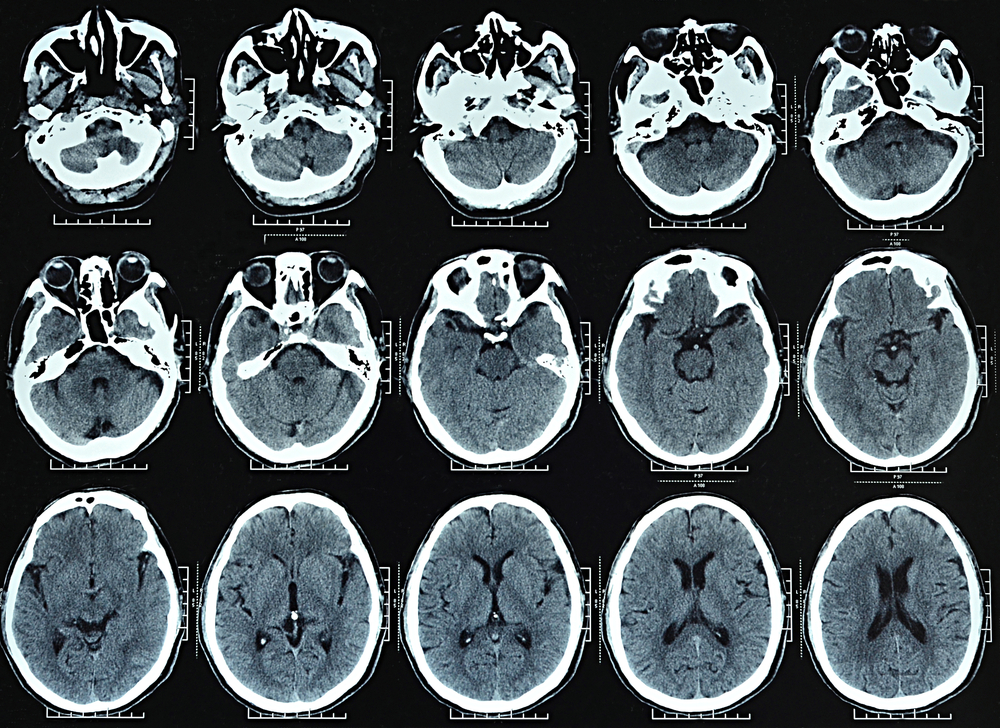

Hydrocephalus is a condition in which CSF accumulates in the brain ventricles, potentially leading to brain damage and death. Hydrocephalus is corrected by placing a VP shunt that drains excess CSF to the abdomen. However, CSF shunts in hydrocephalus patients fail frequently, usually by obstruction, and are difficult to diagnose. Since catheter replacement requires surgery, a need for shunt revision must be established.

Current methods for detecting shunt malfunction do not meet the needs of hydrocephalus patients. Physical examination, including pumping of the shunt reservoir, is unreliable. CT remains the gold standard, but is expensive and results in repeated radiological exposures of patients, many of whom are children. Radionuclide shunt flow testing is invasive and poses a risk of infection, and new technologies under development are complex, lacking in precision or require implantation and have not reached the clinic.